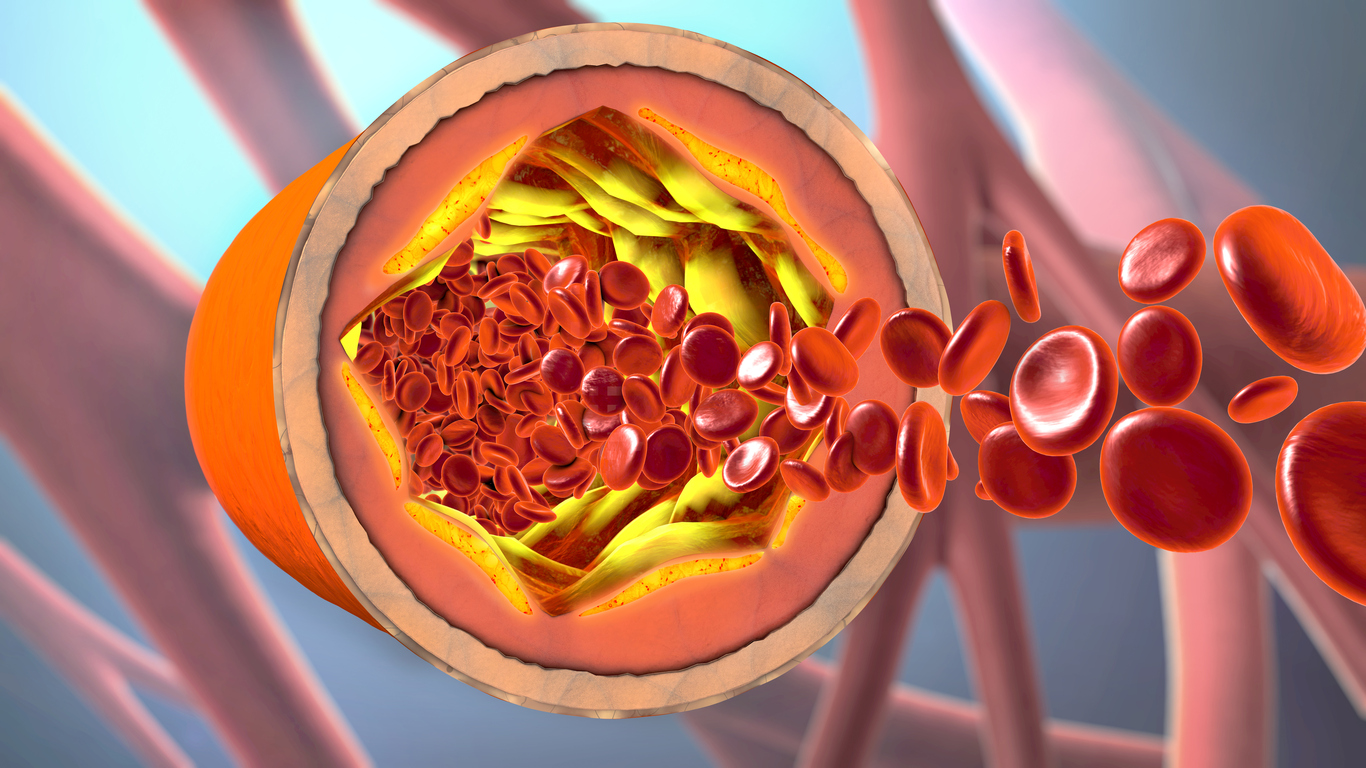

Η λιποπρωτεΐνη υψηλής πυκνότητας (HDL) αναφέρεται συχνά ως “καλή” χοληστερόλη. Η ύπαρξη υψηλών επιπέδων HDL βοηθά στην μεταφορά της χοληστερόλης από τις αρτηρίες σας στο ήπαρ, όπου μπορεί να χρησιμοποιηθεί, ή να αποβληθεί από τον οργανισμό, ανάλογα με τις ανάγκες του.

Η υψηλή καλή χοληστερόλη (HDL) έχει επίσης αντιοξειδωτικές και αντιφλεγμονώδεις επιδράσεις και συνδέεται με μειωμένο κίνδυνο καρδιακών παθήσεων. Οι περισσότεροι ειδικοί στον τομέα της υγείας συνιστούν ως ελάχιστο επίπεδο HDL στο αίμα τα 40 mg/dl στους άνδρες και τα 50 mg/dl στις γυναίκες.